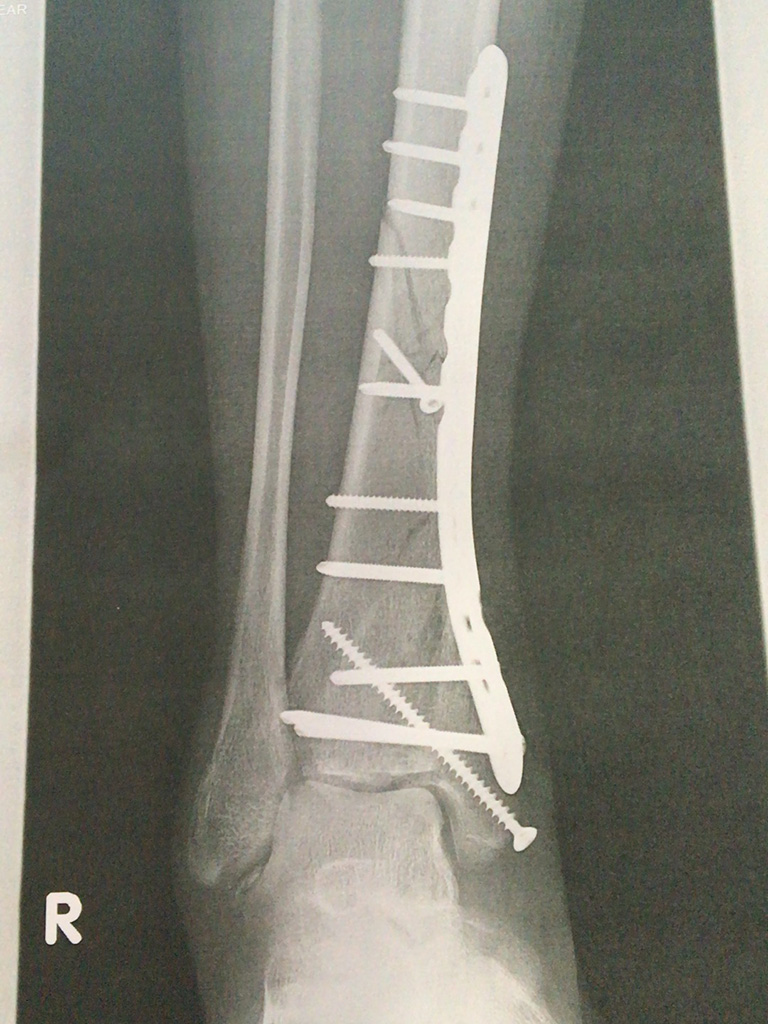

退院するに当たって昨日最後に撮ったレントゲンのコピーをもらったけど、相変わらず見ても治っているのかいないのか…(笑)

昨日から右足は10kgまで荷重を掛けても良いということになっていて、骨に直接力が加わると治りっぷりも加速するらしく、一昨日よりも明らかに痛みが減っているし、膝から下のいろんなところの動きがスムーズになってきている。